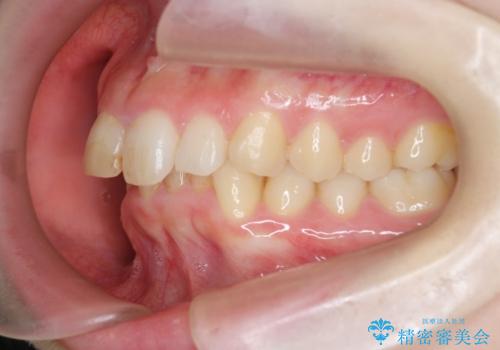

前歯のがたつき 深い噛み合わせを改善したい

- 「前歯のガタつきをきれいにしたい、噛んだ時に下の前歯が見えないことを改善したい」とマウスピース矯正を希望され来院されました。

マウスピースに加え、矯正用マイクロインプラントやゴムを併用し、がたつきや噛み合わせの深さを改善していきます。

ゴムかけやマウスピースの装用時間、しっかりとマウスピースをはめ込むチューウィーをしっかりと使用したことで良好な治療結果を得ることができました。